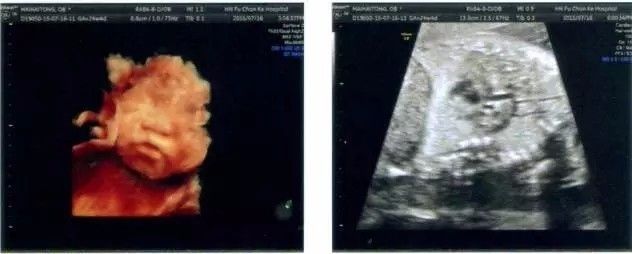

▲主动脉缩窄伴室间隔缺损,症状随年龄增加而加重,可出现呼吸困难、头疼、间歇性跛行

▲法洛四联症,此疾病重症者有25%~35%在1岁内死亡,90%病人会夭折。